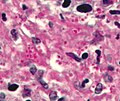

Microscopic

Features:

- Often in yeast form - in tissue, spherical, 2-5 micrometres.[9]

- Intracellular[10] - may be within macrophages that form a granuloma.

- Nice bright red on PAS-D.

- Have a "central dot".[11]

Images

- Histoplasma in granuloma pas-d.jpg

Histoplasmosis - granuloma - PASD stain. (WC)

- Histoplasma pas-d.jpg

Histoplasmosis - PASD stain. (WC)

- Histoplasma pas-d small.jpg

Histoplasmosis - cropped - PASD stain. (WC)